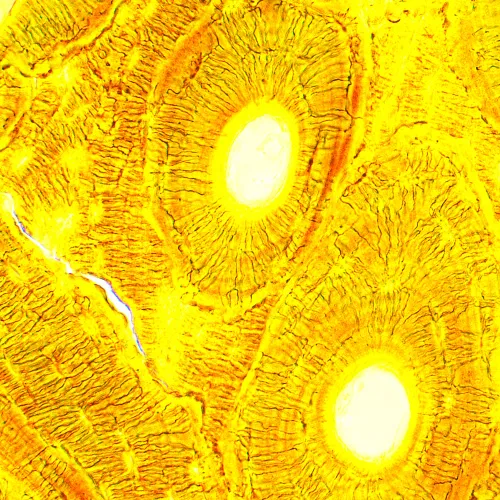

Il microscopio biologico MAGUS Bio 250B è uno strumento ottico utile per lo studio di sottili campioni trasparenti e semitrasparenti. La principale tecnica impiegata per le osservazioni è la microscopia in campo chiaro. Questo microscopio può essere equipaggiato con accessori aggiuntivi per le osservazioni in campo oscuro, con tecniche di contrasto di fase o con luce polarizzata. Grazie alle ottiche di alta qualità, con elementi aggiuntivi in grado di espanderne le capacità, ai meccanismi facili da usare e al suo design intelligente, questo microscopio è una scelta eccellente per le attività di laboratorio, per la ricerca e l’insegnamento.